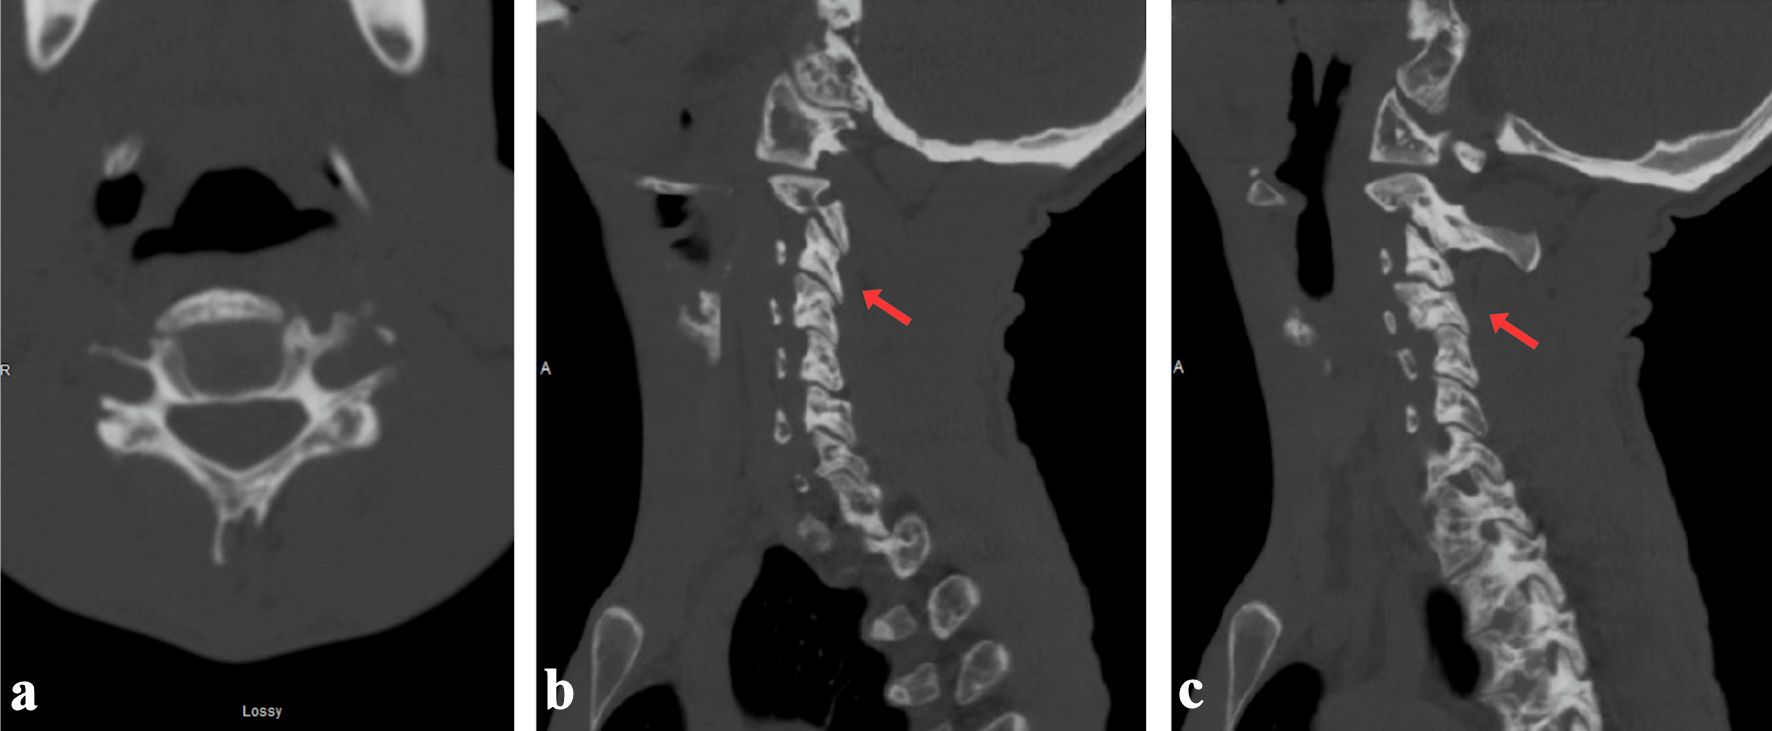

Magnetic resonance imaging (MRI) confirmed a spinal cord contusion at the C3-4 level, evidenced by a focal T2-hyperintense signal. It also revealed significant ligamentous injury, including damage to the posterior longitudinal ligament at C4, attenuation of the ligamentum flavum at C3-4, traumatic widening of the left C3-4 facet joint, and a small C4-5 epidural hematoma (Fig. 2).

Figure 2. T1- (a), T2- (b) and STIR-weighted (c) magnetic resonance (MR) images showing mild spinal cord edema at the C3-C4 level and the left ventral aspect of the cord with thin posterior epidural hematoma. Posterior longitudinal ligament injury is seen at C4, with suspected ligamentum flavum injury at C3-C4. Interspinous ligamentous injury extends from C3 to C6 with left facet capsular injury from C3-C4 and C4-C5 (red arrows). STIR: short tau inversion recovery.